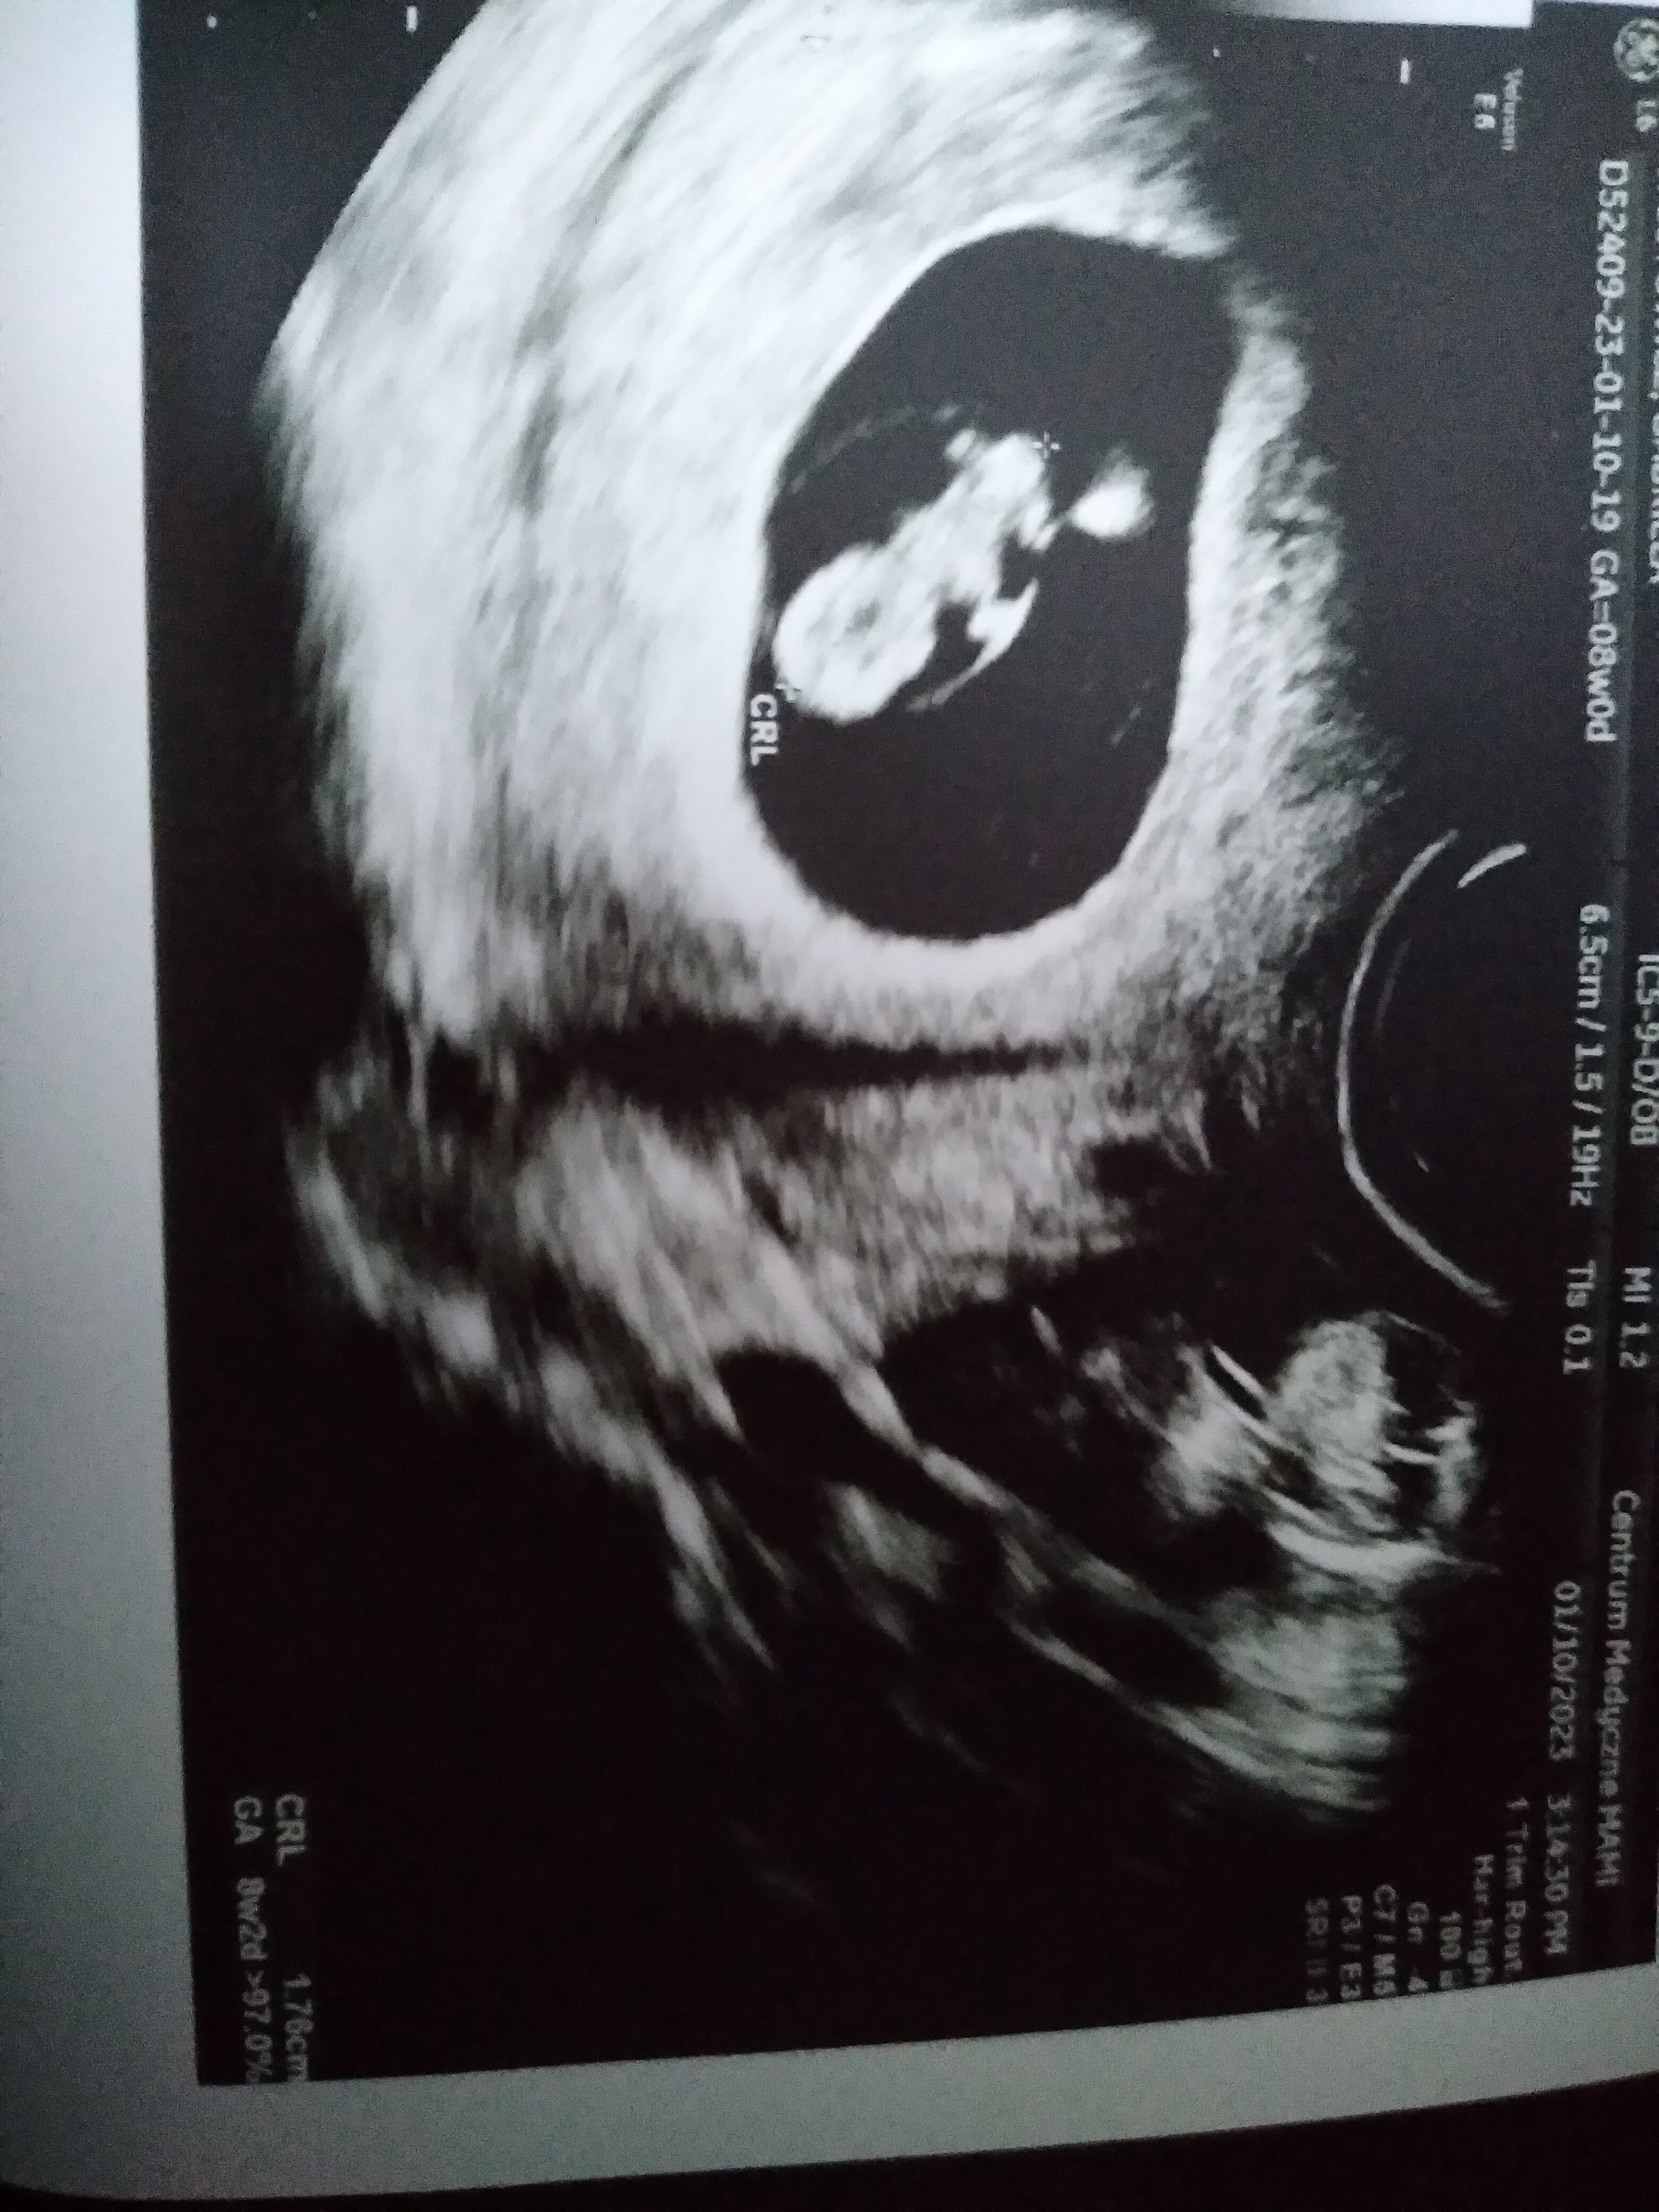

Tez prawda lekarz zarysowuje myszka od do tak jak widzi w tym danym momencie i tez mysle ze to nie musi byc 100% dokladneJa się zastanawiam na ile doskonały jest pomiar tych zarodków

to chyba nie ma nic do rzeczy w moim przypadku bo mi wiek ciąży wyliczyło właśnie z tej długości. W sensie komputer. Oczywiście może być w rzeczywistości inny wymiar zarodka i tym się niespecjalnie przejmuje, ale jednak komputer uznał ze te 8,3 mm to jest 6+5Ja się zastanawiam na ile doskonały jest pomiar tych zarodków

Mój ginekolog ma tak ze mierzy CRL i samo wskakuje od razu w programie jaki dokładnie to wiek ciąży